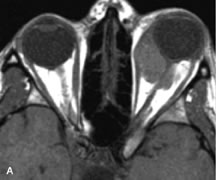

Fig. 20. A. T1-weighted MR scan demonstrates nodular enlargement of both medial rectus muscles (arrows). B. T1-weighted fat-suppressed contrast-enhanced scan confirms the presence of small metnstatic deposits within the muscles (open arrows).

Breast carcinoma metastatic to the orbit has been demonstrated to be hypointense to the surrounding orbital fat on T1-weighted studies and hyperintense on T2-weighted images and has an affinity to the extraocular muscles (Fig. 20).50,64 The MRI characteristics of prostate carcinoma metastatic to the orbit have been described as involving the greater and lesser wing of the sphenoid, orbital roof, and optic canal. Diffuse bone hypertrophy with isointense or slightly hyperintense tissue on T1-weighted images represents the osteoblastic carcinomatous bone infiltration. Contrast enhancement is variable on T1-weighted and fat-suppressed images.65